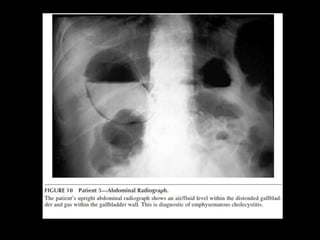

EMPHYSEMATOUS CHOLECYSTITIS

•   Emphysematous cholecystitis < 1%

•   ATC: elderly, male, dbt

•   Mortality rate: 15% (1.4 cholecystitis)

•   TTO: CX because of perforation

•   Test of choice: Abdominal RX

GAS IN THE GALLBLADDER WALL IS

PATHOGNOMONIC FOR

Emphysematous cholecystitis < 1% • ATC: elderly, male, dbt • Mortality rate: 15% (1.4 cholecystitis) • TTO: CX because of perforation • Test of choice: Abdominal RX